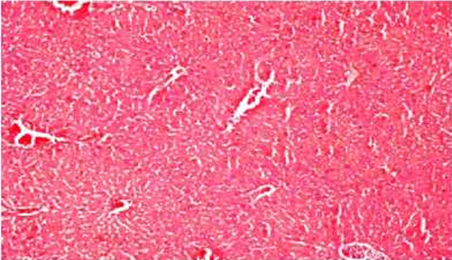

Внешний вид нормальных и деградированных тканей различных органов показан на рисунках. Наблюдались органы: печень, головной , легкие.

Нормальная ткань Печень при увеличении х400